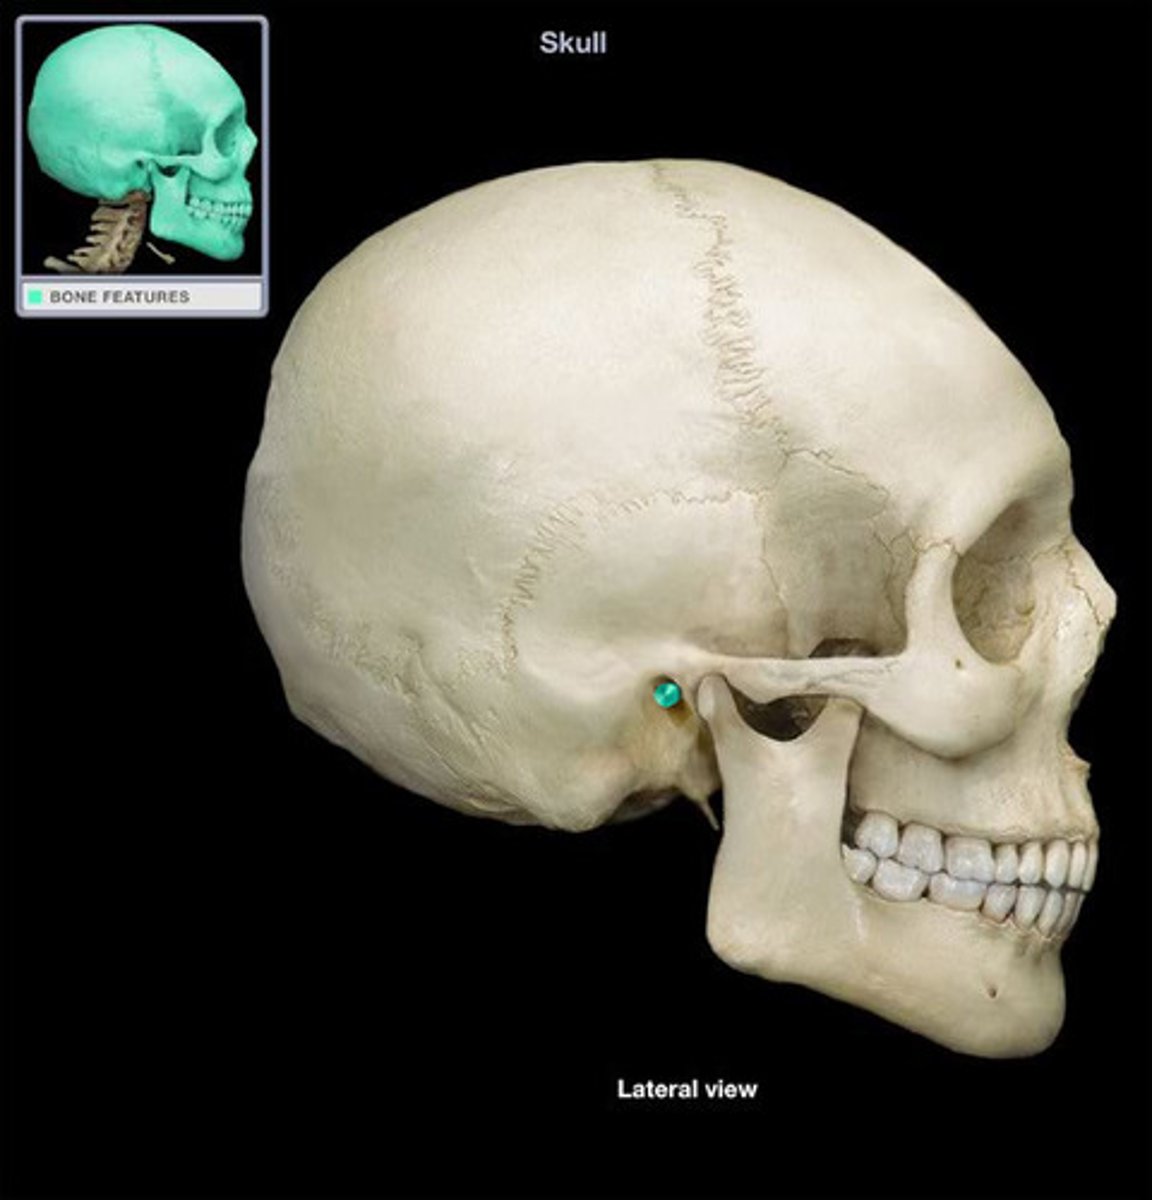

External acoustic (auditory) meatus

Mastoid process

Styloid process

Zygomatic arch

Carotid canal

Zygomatic process

Mandibular fossa